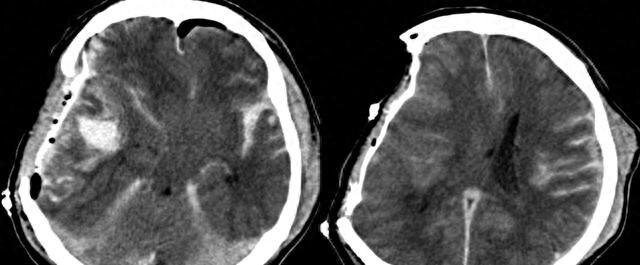

33 года назад людям стало известно об открытии огромной важности. Пациент, страдавший головными болями и эпилептическими припадками, привлек широкое внимание медицинского сообщества. После планового обследования его мозга врачи с удивлением обнаружили, что его мозг был практически замещён жидкой тканью, что свидетельствует о тяжёлом отёке мозга и крайне серьёзном повреждении коры головного мозга. Результаты КТ оказались ещё более невероятными. Внутри его головы не было практически никаких неповреждённых мозговых тканей. Эта ситуация повергла врачей в глубокое замешательство. Как вообще может человек с практически отсутствующим мозгом жить как нормальный человек?

Данный пациент не только женился и завёл детей, но и сдал экзамен на государственную службу. Пока он не приехал лечиться от болезни, будучи взрослым, его повседневная жизнь, казалось, не сильно страдала.